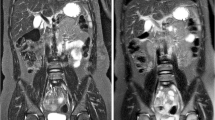

In diffusion-weighted MRI (DWI-MRI), the signal intensity of a tissue is determined by the degree of Brownian motion of water molecules when a magnetic field gradient is applied. DWI provides information regarding tissue cellularity and cell membrane integrity and is already an established imaging sequence used in the assessment of brain lesions. DWI is gaining acceptance in MSK imaging as an aid to help distinguish between malignant and non-malignant lesions, including benign osteoporotic collapse vs. malignant vertebral compression fractures and benign vs. malignant soft tissue tumours (Karchevsky et al. 2008). Malignant tissues show restricted diffusion due to the high cellularity of tumour tissue, irrespective of the degree of associated oedema and necrosis (Fig. 7.6). There is some controversy in the literature regarding accuracy of DWI sequences for differentiating between TB spondylodiscitis and malignancy in the spine, although it appears that DWI can be used as a tool to help differentiate between pyogenic osteomyelitis and malignancy (Herneth et al. 2008).

(a) Coronal T1W image of the sacrum showing ill-defined hypointensity (arrow). (b) Axial DWI of the pelvis showing marked hyperintensity (restricted diffusion) in the sacrum of the same patient (arrow), confirming the presence of sacral metastases. An insufficiency fracture of the sacrum would show bone marrow oedema but would not show restricted diffusion